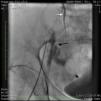

Case reportA 50-year-old Caucasian woman with hypertension, tobacco abuse, and peripheral arterial disease with life-limiting claudication had stents placed in bilateral 80% ostial iliac artery lesions two months previously. She was also noted to have a CTO of the left SFA at the ostium with no obvious stump (Figure 1) which was reconstituting distally via collaterals just above the popliteal artery (Figures 2 and 3). Due to her ongoing symptoms despite optimal medical therapy, it was decided to intervene on the SFA. Since there was no obvious stump of the occluded SFA proximally, we decided to approach the CTO through a retrograde approach.

An angiogram from the left femoral sheath at this time showed retrograde filling of the distal and proximal SFA (Figure 4) and then the dissection plane in the EIA with a wire tip perforation and bleeding (Figures 5 and 6) to the retroperitoneal region at the external iliac artery with displaced bladder (Figure 6). Protamine was given to reverse the heparin and a 7-minute balloon inflation was performed in the distal SFA using a 5.0 mm×40 mm Evercross balloon (ev3, Plymouth, MN) to stop the retrograde bleeding. On repeat angiography, the distal SFA CTO was reoccluded and the dissection plane appeared to be sealed, with no further bleeding into the retroperitoneal region (Figures 7 and 8). Other than mild nausea after protamine, the patient reported no major symptoms during this procedure. When activated coagulation time was 130 s, the femoral and popliteal sheaths were removed. A 3-g/dl drop in hemoglobin was noted after the procedure that remained stable over the next two days. Popliteal and pedal pulses were palpable and unchanged following the procedure.